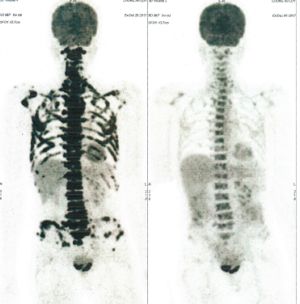

Below are some of the cases, from more than 80 cases we have treated so far with good results. When reading the PET/CT scans, the picture on the left is before treatment, and the picture on the right is after treatment. The intensity of black represents the activity of the cancer, but some black areas are not cancer: brain, heart, radioactive urine in bladder. For the heart, the intensity of black depends on the number of hours of fasting: if more than 10 hours, the heart is not even black, but if fasting is less than 6 hours, it is very black. The intensity of black in the brain can be variable in different scans depending on the brain activity at the time of the scan. The intensity of black in the radioactive urine can also be variable due to the hydration of patients and the time of injection of diuretic.

CASE NO: 3 (PROSTATE CANCER)

A middle-aged man with castration resistant prostate cancer, having failed all currently available cancer treatment, was very weak, and getting worse every day. The PET/CT scan showed he had massive bone metastases. After a few treatment, all the bone metastases went into remission. About 6 months later, he is still in remission.

CASE NO: 4 (PROSTATE CANCER)

A middle-aged man with castration resistant prostate cancer and massive bone metastases, failed all currently available cancer treatment, including with the new and expensive drug XTANDI. After a few treatment, most of the bone metastases went into remission, and the remaining ones are less active. Treatment will continue. Cases no: 3 and 4 show that terminal prostate cancer today can be cured with our new cancer treatment.